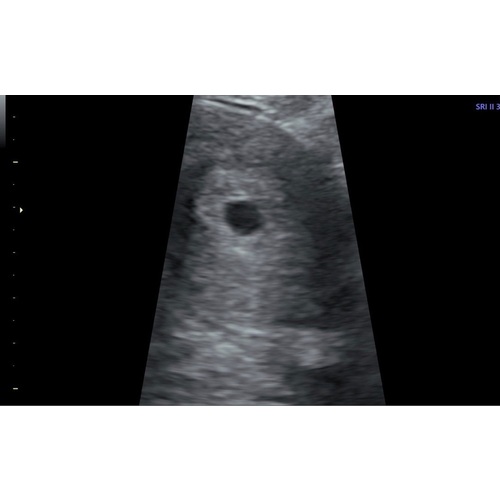

Het lijkt me eigenlijk wel logisch dat je verkeerd gerekend hebt. Als je al 2,5 jaar probeert en nu dus een keer zonder testen eindelijk wél zwanger bent geworden, zit je lijf waarschijnlijk net anders in elkaar. Zoals deze foto zag mijn eerste (te vroege) echo er ook uit. 10 dagen later een gezonde zwangerschap te zien :)